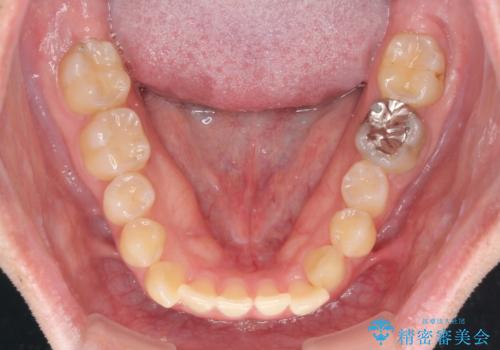

- 前歯のクロスバイトを気にして来院された患者様です。

骨格的には問題がなかったため、インビザラインを用いて咬み合わせを改善していくこととしました。

インビザライン特有の、奥歯の咬み合わせの問題もなく、しっかりと歯列を改善することができました。

舌側転位している上顎側切歯(内側に引っ込んでいる真ん中から2番目の歯)は、インビザラインが最も移動を苦手とする歯であり、これ以上の改善を望まれる場合にはワイヤー矯正、あるいはワイヤー矯正の併用をお勧めいたします。